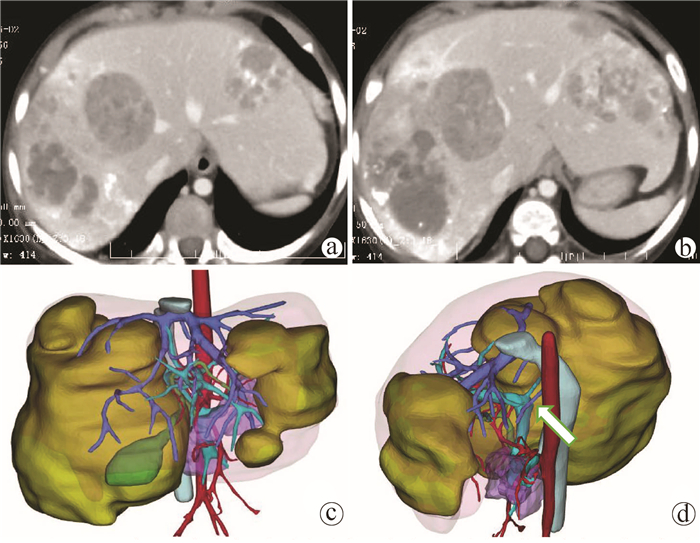

肝脏三维可视化重建技术在儿童复杂肝母细胞瘤肝切除术中的应用价值

赵頔, 叶进冬, 李华丽, 金奎, 刘翔, 李潇然, 段留新, 刘军桂, 吕伟, 段伟宏, 刘全达

2021, 37(9): 2130-2135. DOI: 10.3969/j.issn.1001-5256.2021.09.025

摘要(1330) HTML (406) PDF (3973KB)(67)

摘要:

目的  探讨肝脏三维可视化重建技术在儿童复杂肝母细胞瘤肝切除术中的应用价值。  方法  回顾分析2018年1月—2020年10月于火箭军特色医学中心实施了以根治性切除为目的的肝肿瘤切除术的30例肝母细胞瘤患儿的临床资料,根据术前是否行肝脏三维重建(IQQA-Liver系统)将所有患儿分为三维重建组(n=15)和对照组(n=15),比较2组患儿围手术期临床参数以及短期预后和随访情况。符合正态分布的计量资料2组间比较采用独立样本t检验,不符合正态分布的计量资料2组间比较采用Mann-whitney U检验。计数资料2组间比较采用Fisher确切概率法。  结果  三维重建组较对照组平均年龄更大[(55.7±10.2)月vs (28.2± 2.7)月]、POSTTEXT Ⅲ/Ⅵ期(12例vs 5例)和肝静脉或下腔静脉受累者(11例vs 3例)更多,差异均有统计学意义(P值均<0.05)。所有患儿均顺利完成手术,2组在出血量、手术时间、肝门阻断次数/时间、行肝段及部分肝切除例数方面,差异均无统计学意义(P值均>0.05)。术后中位随访时间9.5个月,三维重建组2例复发,分别于术后10个月和12个月确诊,目前继续化疗中;对照组4例复发,高于三维重建组(P=0.651),其中2例在术后7个月复发接受肝移植存活至今,另有2例复发后短期内死亡。  结论  三维可视化重建技术有助于更安全精准实施复杂儿童肝母细胞瘤肝切除术,尤其是可以使部分POSTTEXT Ⅲ/Ⅵ期患者安全实施扩大肝切除,从而避免行肝移植。